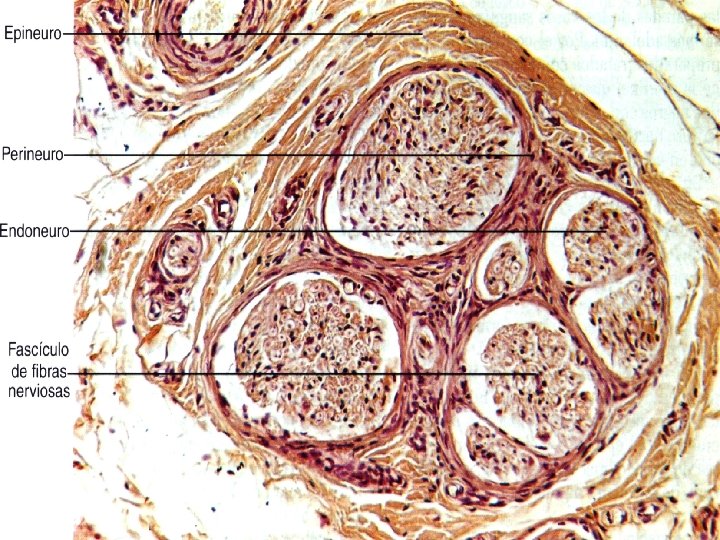

Axones y nervios